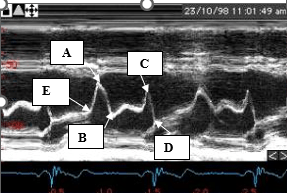

The name for this indirect sign of aortic valve regurgitation on M-mode.

What is anterior mitral valve leaflet diastolic fluttering?

Letters A and C represent these waveforms.

What is a- rapid or early filling and c - atrial systole or atrial kick?